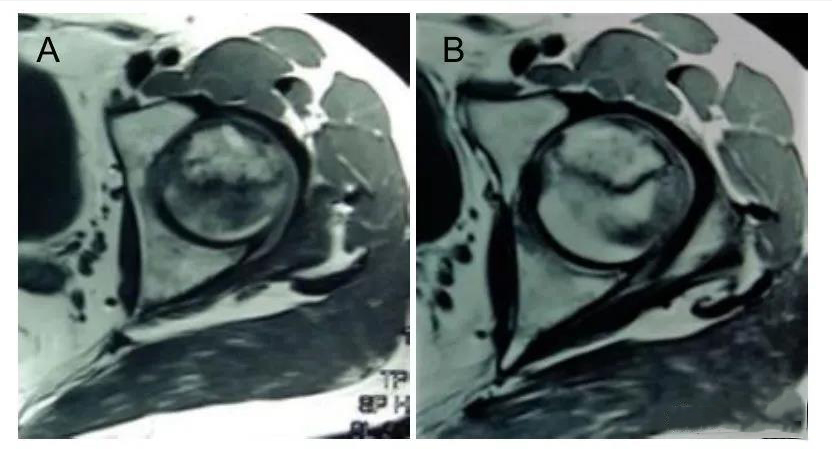

此外,MRI片上坏死面积较术前明显减小,治疗前坏死面积为(31.0±5.3)mm2,治疗后为(24.3±3.5)mm2,具有差别意义。

图A:MRI图像股骨头坏死;

图B:显示治疗后股骨头坏死面积缩小。